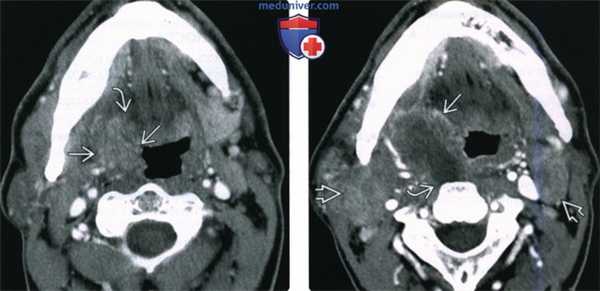

(Слева) При МРТ Т2ВИ FS в аксиальной проекции у пациента 50 лет с объемным образованием левой небной миндалины визуализируется экзофитная опухоль В неоднородной структуры. Ровный боковой край опухоли означает отсутствие глубокой инвазии.

(Справа) При МРТ Т1 DB С+ FS в корональной проекции у этого же пациента визуализируется крупная опухоль (плоскоклеточный рак) левой небной миндалины, экзофитного характера, имеющая ножку. МРТ позволяет отчетливо продемонстрировать отсутствие глубокого распространения опухоли в медиальную крыловидную мышцу. Стадия опухоли соответствует T3N0M0 (третья стадия заболевания), пациенту была назначена химиотерапия.

(Слева) При корональной ПЭТ/КТ у пациента с вновь возникшим пальпируемым образованием правой половины шеи определяется повышенное накопление ФДГ в крупном конгломерате лимфоузлов второго уровня, а также асимметричное накопление ФДГ в плоскоклеточном раке правой миндалины. Обратите внимание на отсутствие изменений со стороны левой миндалины.

(Справа) При аксиальной ПЭТ/КТ у этого же пациента определяется несимметрично повышенное накопление ФДГ в правой небной миндалине В по сравнению с противоположной стороной. При КТ с КУ не было обнаружено патологических изменений в этой области. Была выполнена биопсия, подтвердился ПКР.